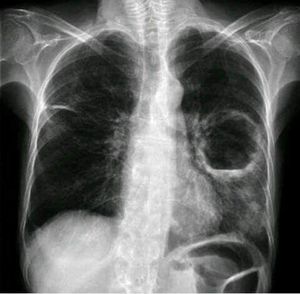

Diagnosis male aged 45